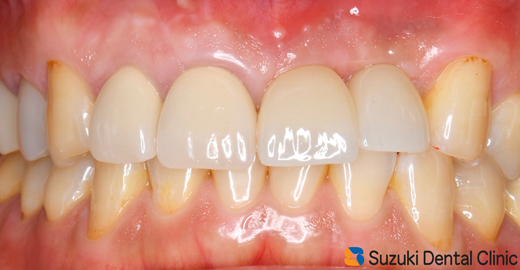

施術より3ヶ月後、インプラント完成。

施術から3ヶ月後、インプラント完成。

適合の良くなかった前歯もセレックを使って、オールセラミックスに順次やり変え。